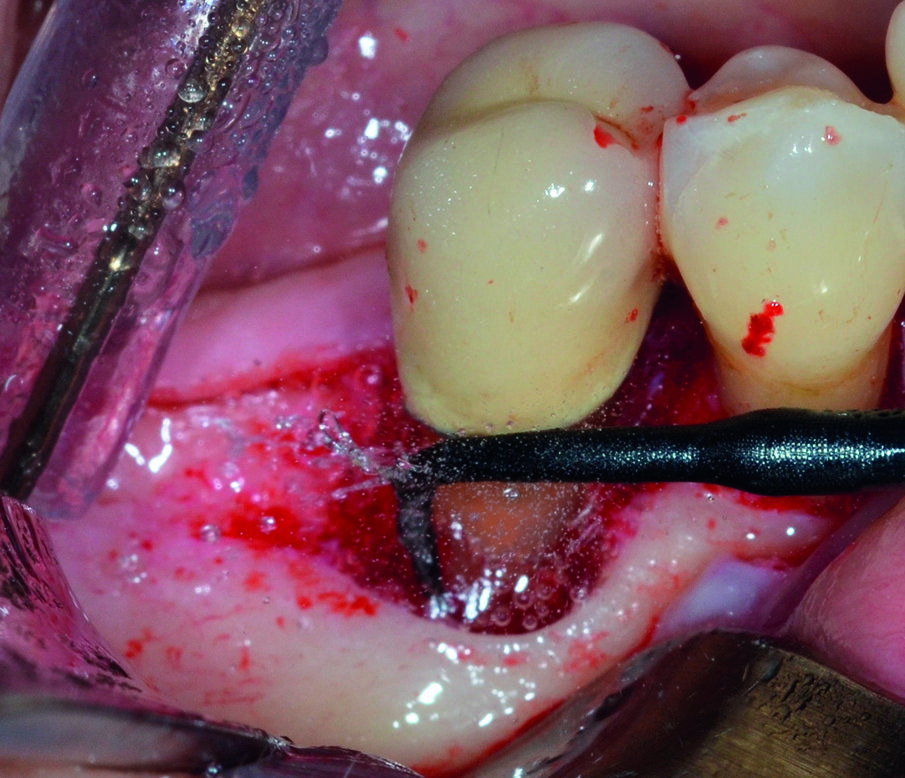

Dopo analgesia locale ottenuta per infiltrazione di Articaina cloridrato 40 mg con epinefrina 1:100.000 viene effettuata l’ incisione di accesso in accordo con il protocollo chirurgico sopra citato (Fig. 4). Al sollevamento del lembo è possibile evidenziare un profondo difetto che coinvolge l’aspetto disto-buccale dell’ elemento 4.5; con una sonda parodontale millimetrata di tipo Williams viene misurata la profondità della componente intraossea (Figg. 5-7). Il debridement della lesione e la decontaminazione della superficie radicolare vengono effettuati mediante una coppia di inserti dedicati montati su dispositivo ad ultrasuoni (ES030LDT ed ES030RDT, Esacrom Srl, Imola, Italia) (Fig. 8).

La particolarità di questi inserti è quella di avere una curvatura orientata verso destra (ES030RDT) e verso sinistra (ES030LDT): in tal modo, risulta molto più agevole operare sul versante buccale o linguale/palatale a seconda dei casi (Figg. 9, 10). Grazie all’effetto combinato della cavitazione ultrasonica e del microstreaming acustico vengono effettuati sia la rimozione del tessuto reattivo che la completa decontaminazione della superficie radicolare (Fig. 11). Al termine del trattamento con ultrasuoni, è possibile valutare l’aspetto intraoperatorio dell’area interessata dal difetto (Fig. 12).